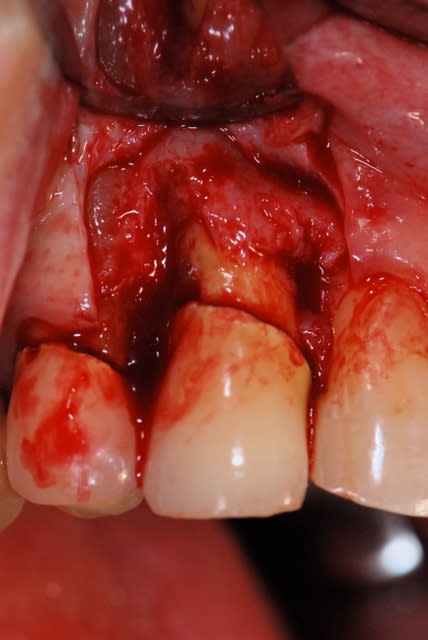

pour candide:

je te propose ce cas que j'ai achevé il y a 2 mois; tu verras que la notion de limite est variable, sauf celle du blocage primaire, d'où cette proposition de mise en esthétique uniquement avec un bon blocage primaire;

pour jeff:

les aléas chirugicaux sont toujours présents, une membrane sinusienne qui se déchire en grand, un pas de vis qui foire, une corticale qui cède, etc

ton cas est obligatoirement aléatoire, il vaut mieux en parler à ta patiente d'abord; elle ne te le reprochera jamais; dans ce cas, je me préparerais à ne faire qu'un comblement avec membrane, mais aussi à poser l'implant et à faire la MEI; ce n'est que mon avis